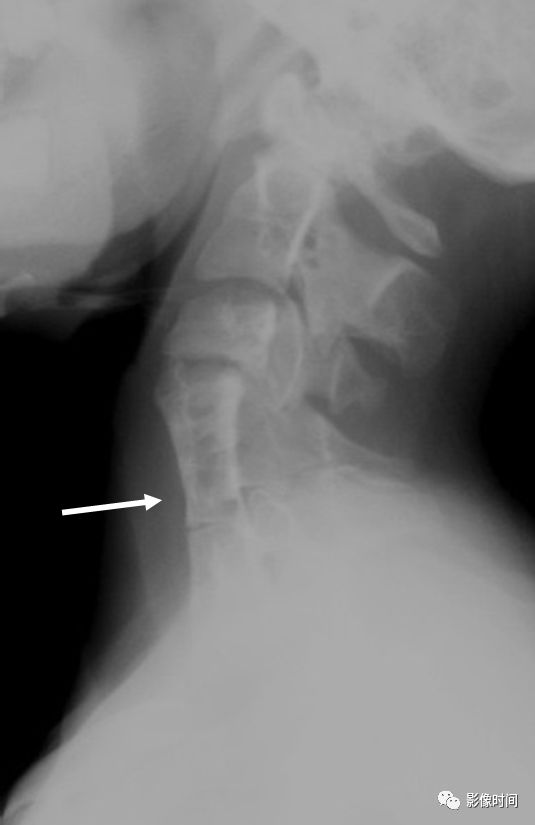

30黄蜂腰征

黄蜂腰征(wasp-waist sign),也译为细腰征

黄蜂腰征是 Klippel-Feil 综合征(先天性颈椎融合畸形)患者的影像学表现。因椎体融合导致受累椎体(融合椎间盘处)的前后径小于邻近未受累椎体的前后径,形似黄蜂的细腰而得名。

典型病例

Klippel-Feil 综合征,颈椎侧位 X 线片示颈 4-6 椎体融合,呈黄蜂腰征。